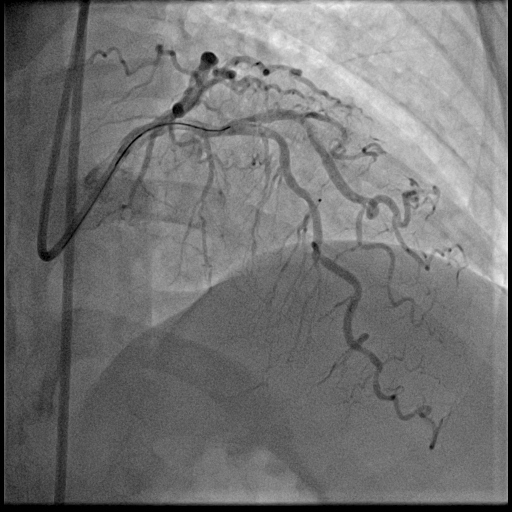

Coronary intervention was performed using an EBU 3.0, 6 Fr guiding catheter via the right radial artery approach. A Runthrough Floppy wire was advanced to the distal first LAD, and a Sion Blue wire to the second LAD. Pre-dilatation of the mid first LAD was performed using a semi-compliant (SC) 2.0 ¡¿ 15 mm balloon at high pressure. Intravascular ultrasound assessment revealed fibrocalcific plaque in both vessels. The vessel reference diameter of the first LAD measured 2.5 mm distally and 3.0mm proximally, with a minimal lumen area of 5.5–6.0 mm©÷ at the ostial segment. The second LAD had a vessel reference diameter of 2.5 mm distally and 2.75 mm proximally. Pre-dilatation of the second LAD was performed using a SC balloon at nominal pressure. Vessel preparation of the first LAD was then performed using a non-compliant (NC) 2.0 ¡¿ 10 mm balloon, followed by a scoring balloon(2.5 ¡¿ 15 mm) inflated at high pressure. The lesion was adequately prepared with minimal recoil and a type B non–flow-limiting dissection observed indicating adequate vessel preparation before DCB angioplasty. Two drug-coated balloons were inflated in the first and second LAD at nominal pressure for 45 seconds each. Similar non–flow-limiting type B dissections were observed in both LADs, with minimal recoil. Final angiographic results were satisfactory showing TIMI 3 flow with no immediate complications. The patient remained asymptomatic and discharged well the following day.